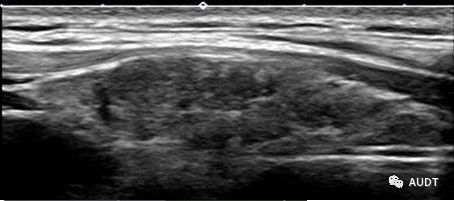

111abc988fe7bfaa8b43747affb004ce.jpg

图22.超声引导颈神经阻滞。清楚显示针尖和针轨道(箭头)及第五颈神经根(白色箭头)与前斜角肌(黄色箭头)的解剖关系。图片由陈定章(Dingzhang Chen)博士提供。